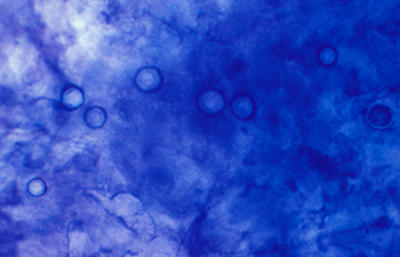

Las imágenes de Acanthamoebas muestran una cápsula circular u ondulada, refringente de color azulado o verde manzana, notablemente más intensa que los materiales y tejidos que la rodean. Suelen medir de 12 a 16 µm de diámetro. El contenido del quiste es azul tenue. (Figura 37 , 38, 39 y 40)

Fig. 37 Blanco de Calcofluor (CW). Original x160

Fig. 38 CW, Original x250

Fig. 39 CW, Original x160

Fig. 40 CW, Original x160